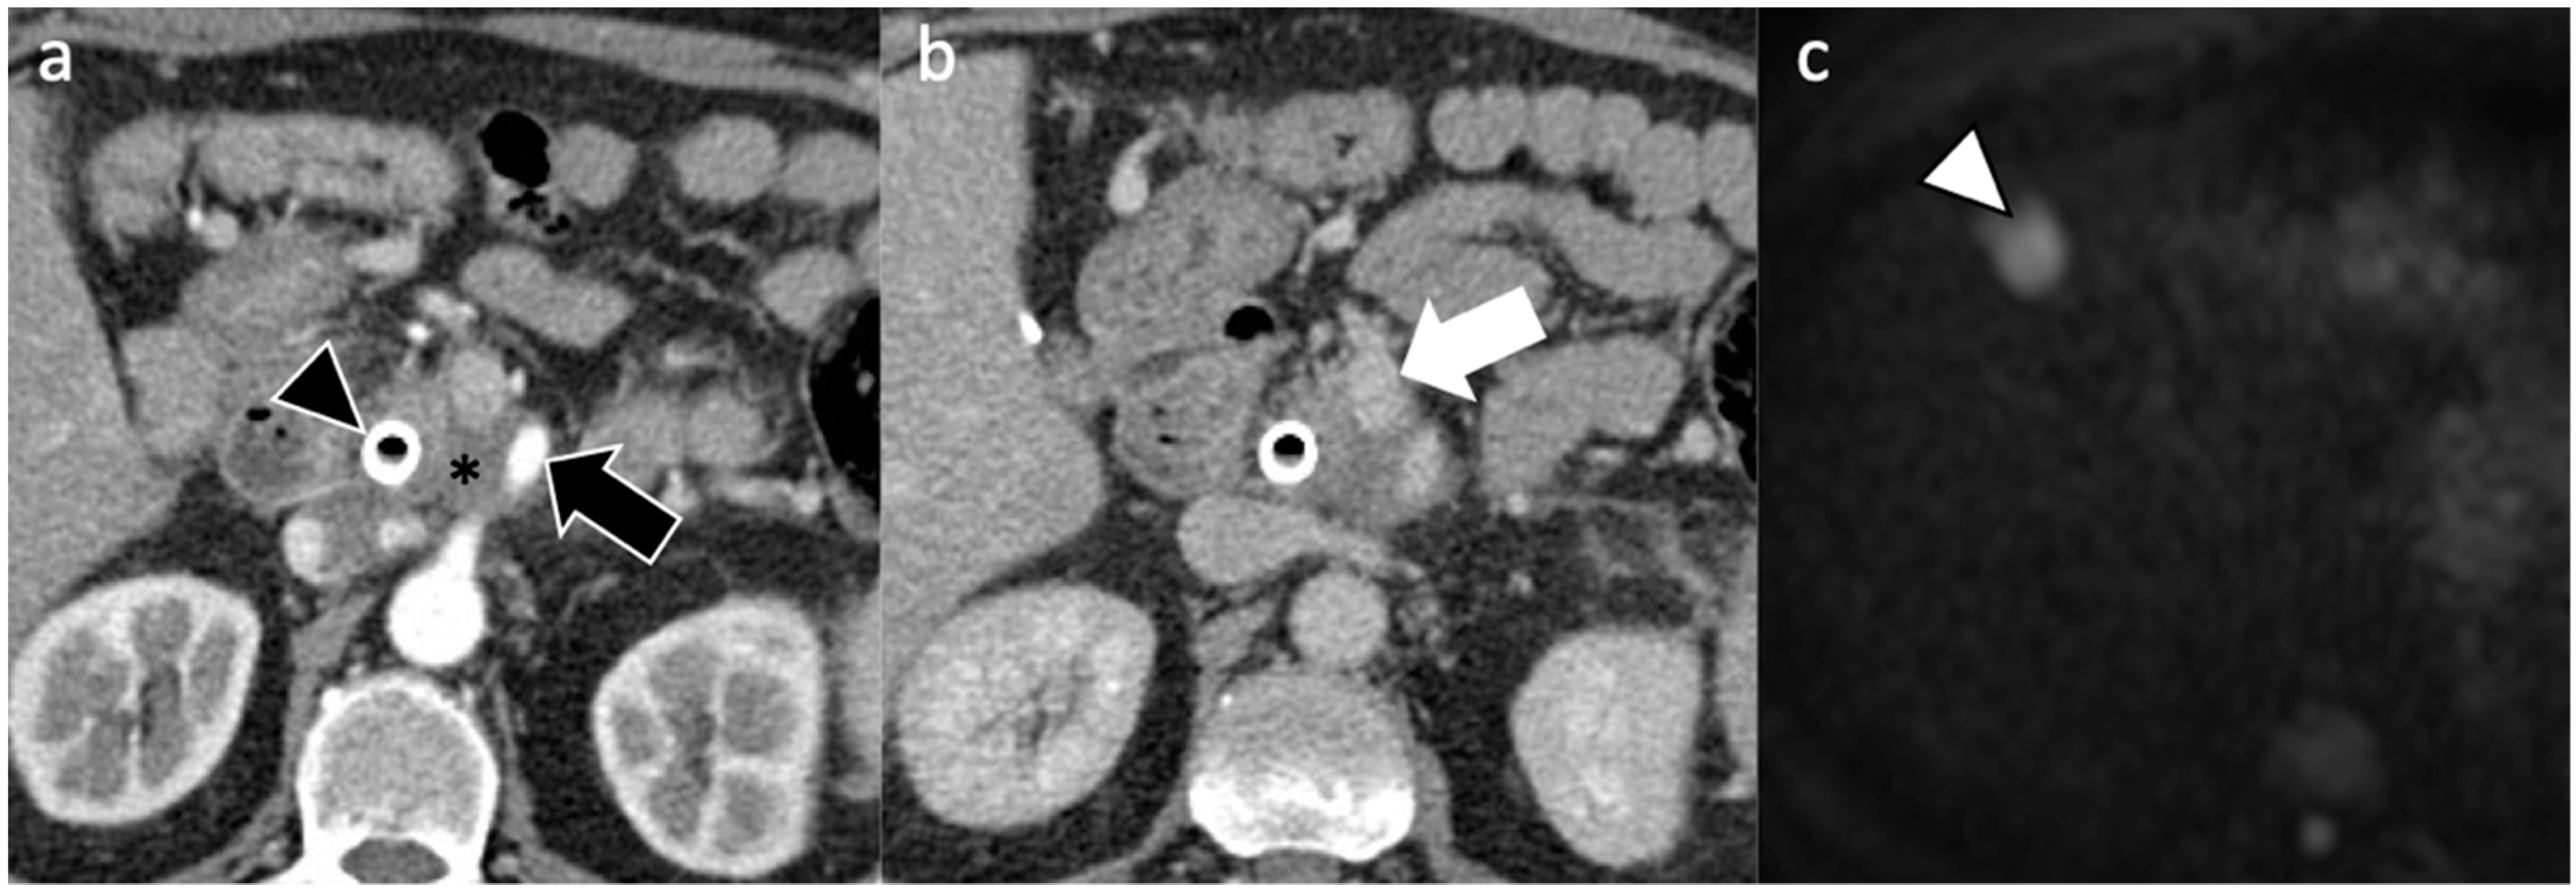

| Imaging Technique | Imaging Findings |

|---|---|

| Ultrasound |

|

| Computed Tomography |

| Magnetic Resonance Imaging |